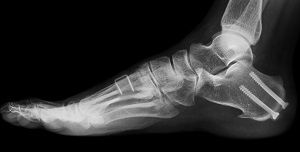

Post-Traumatic Reconstruction of the Foot and Ankle

Post-traumatic reconstruction of the foot and ankle is a surgical procedure performed for the correction...